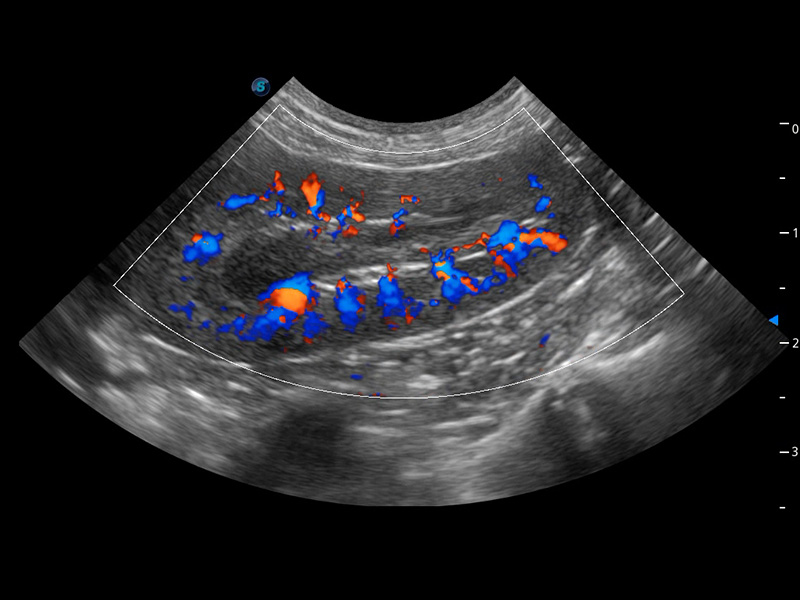

ProPet 60 作为一款高端台式动物超声设备,为动物医生的日常诊断提供了一系列贴合动物临床需求、解决临床实际问题的高级成像功能。凭借全系列高清探头,满足医生对腹部、心脏、生殖、浅表、肌骨等成像的所有需求,切实帮助您提升检查效率,提高诊断信心。

动物是人类最亲密的朋友和最值得信赖的伙伴。美狮贵宾会官网也一直致力于探索动物专用的超声影像解决方案。 全新推出的ProPet系列,是美狮贵宾会官网在动物超声影像智能化、专业化、精准化的一次跨越式革新。动物不能用言语来表述自己的不适,通过超声影像,ProPet系列搭建了动物医生与不同物种沟通的“桥梁”,为动物医生注入了“治愈之力”。